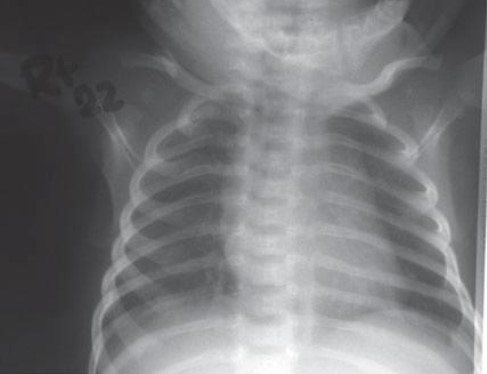

Common X-ray Findings: